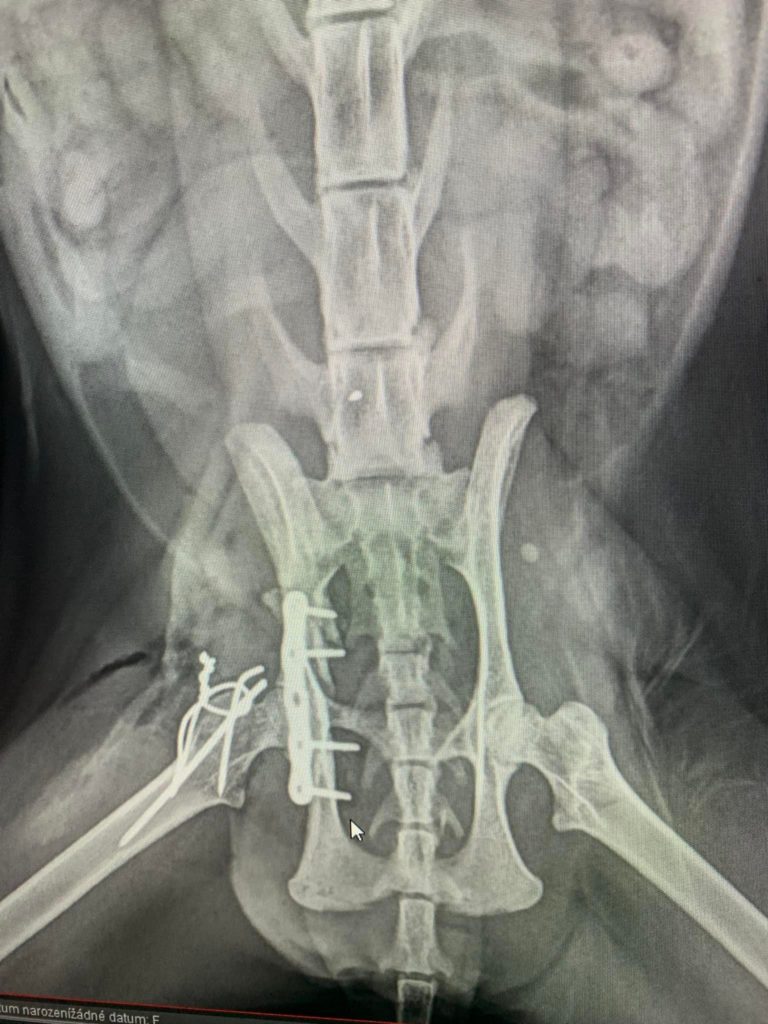

‼MOUROVATÁ KOČIČKA SONETKA SE VE STŘEDU PODROBILA OPERACI PÁNVE. KE ZRANĚNÍ PŘIŠLA DÍKY AUTONEHODY PŘED VÍCE NEŽ TŘEMI TÝDNY. ZLOMENINA PÁNVE SE VE VĚTŠINĚ PŘÍPADECH LÉČÍ KLIDEM, DOKUD SE SAMA NEZHOJÍ. OPERACE OVŠEM V PŘÍPADĚ SONNETKY, KTERÁ STÁLE TRPĚLA BOLESTMI, ...